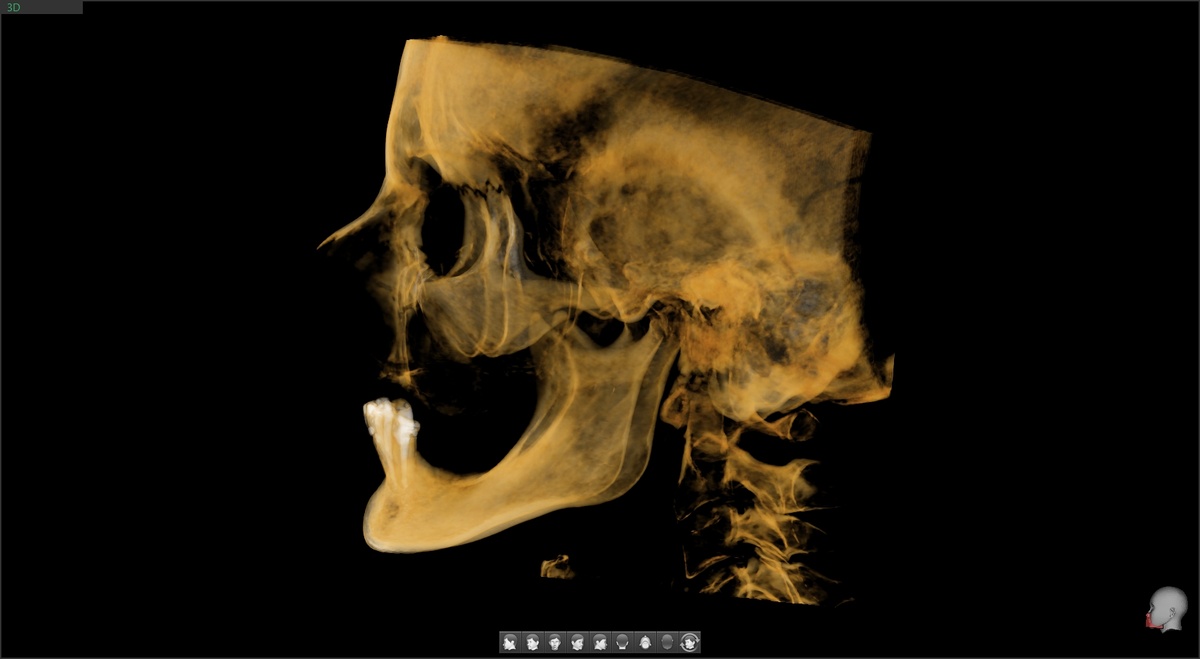

Посмотрите на скрины КТ верхней челюсти (листайте):

Кости нет. Можно сказать прямо - альвеолярный отросток на грани исчезновения, то, что от него осталось, костью полноценной не назовёшь.

Пациентка длительное время пользовалась съёмными протезами - полный съёмный на верхней челюсти, частичный - на нижней. Под давлением протезов кость атрофировалась. Не фигурально - объективно. Даже самые маленькие имплантаты некуда устанавливать.

По верхней челюсти вердикт однозначный - за реабилитацией не к нам.

Здесь нужны скуловые имплантаты - длинные конструкции, которые устанавливаются в скуловую кость, минуя кости челюсти. Мы такие операции не проводим, пока что. Нужна ещё одна клиника для этого дела, в нашу не поместится операционная с полноценным наркозом. А без лицензии на анестезиологию и реаниматологию мы дже седацию делать не будем, это противозаконно и чревато. Но мы движемся в нужном направлении.